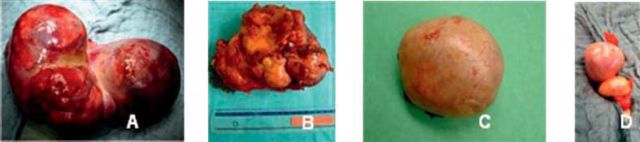

Foram submetidas a biópsia por agulha, antes da cirurgia, duas adolescentes de 13 e 15 anos com disgerminoma. Em 12 doentes a abordagem inicial foi cirúrgica. O procedimento cirúrgico efectuado variou de acordo com o tipo de lesão: ooforectomia (7/14), quistectomia (2/14), anexectomia (1/14), anexectomia e vaginostomia (1/14), anexectomia e estadiamento cirúrgico (2/14) e ressecção alargada de massa pélvica com estadiamento cirúrgico (1/14). Na Figura 2 mostram-se algumas das peças operatórias excisadas. Duas doentes foram enviados de outro Hospital, tendo sido já feita uma abordagem cirúrgica inicial, uma ooforectomia para teratoma cístico maduro, que nos foi enviado por suspeita de lesão no ovário contralateral, e outra ooforectomia laparoscópica de tumor maligno.

Figura 2 - A - Disgerminoma sem invasão; B - Disgerminoma com invasão circundante; C e D - Teratoma